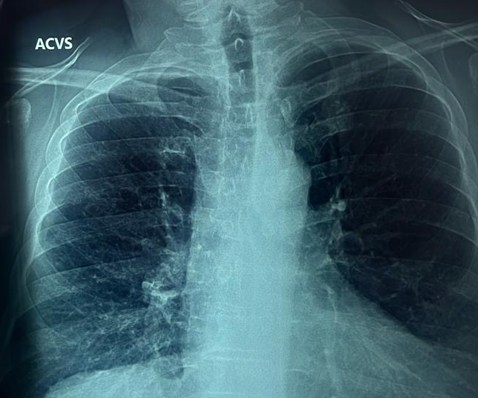

El médico especialista en neumología de la Clínica de Especialidades “Indianilla”, Jorge López de la Cruz, explicó que la EPOC es una enfermedad patológica. La cual se caracteriza por reducir el flujo de aire y atacar principalmente a los bronquios. Ello deriva en múltiples problemas respiratorios.

“Las consecuencias a nivel fisiológico son, en principio, la inflamación y obstrucción de los bronquios. En algunos pacientes puede llegar a producir enfisema pulmonar. Es decir, la destrucción de las paredes de los alvéolos (pequeños sacos de aire en los pulmones) que provocan que los pulmones dejen de cumplir con su función principal: tomar oxígeno del aire para que llegue a la sangre y eliminar el dióxido de carbono del cuerpo”, explicó.